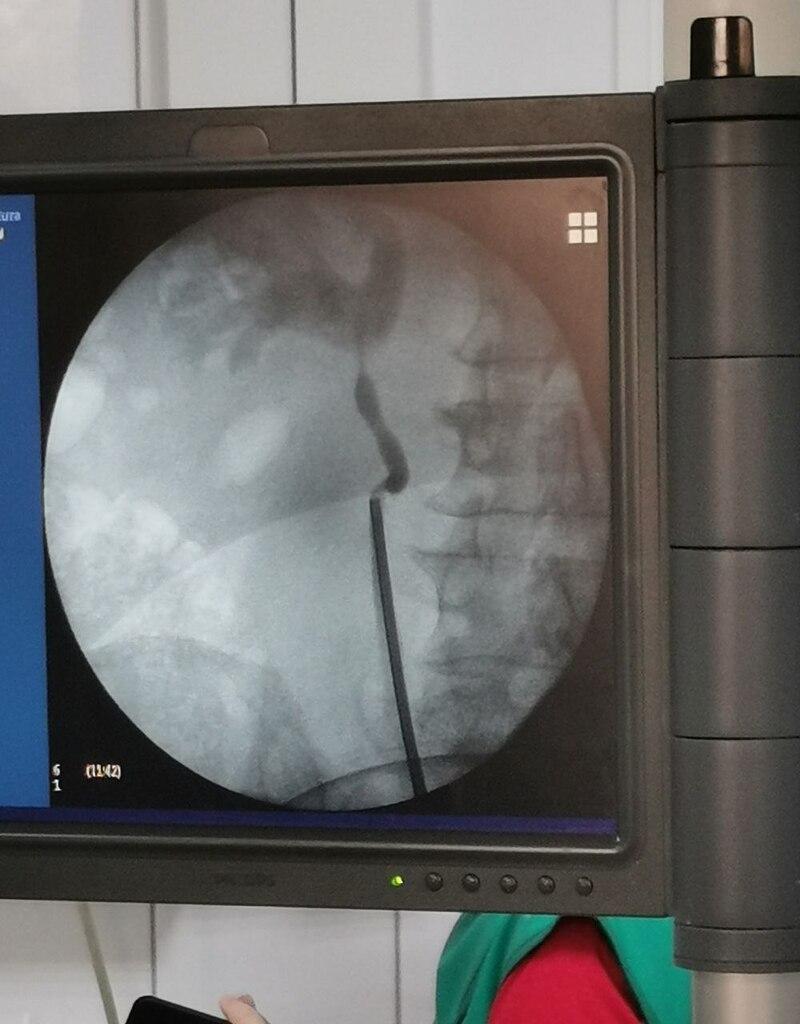

10 октября, в пятницу в отдалении урологии № 1 ПОКБ им. Н.Н. Бурденко врачами-урологами проведена клиническая апробация фибронефро и фиброцистоскопов Hugemed, и впервые выполнены операции по лазерному дроблению камней с использованием данных эндоскопов.

«Одним из преимуществ данных одноразовых эндоскопов является разные точки выхода рабочего канала. Данная возможность имеет значение при сложных или индивидуальных вариантах строения полостной системы почек. Так же, отмечу удобную опцию - активная аспирация, интегрированная в ручку фиброцистоскопа», - объясняет Михаил Миронов, заведующий отделением урологии № 1.

В отделение урологии областной больницы за месяц поступает порядка 100 пациентов с мочекаменной болезнью, которым необходимо проведение лазерной литотрипсии, в том числе фибронефролитотрипсий (РИРХ). Лазерное дробление камней внутри почки  с доступом через мочеиспускательный канал и мочеточник – самый современный  и технологичный  метод лечения мочекаменной болезни, позволяющий  практически полностью  отказаться от «открытых», лапароскопических операций и ДУВЛ.